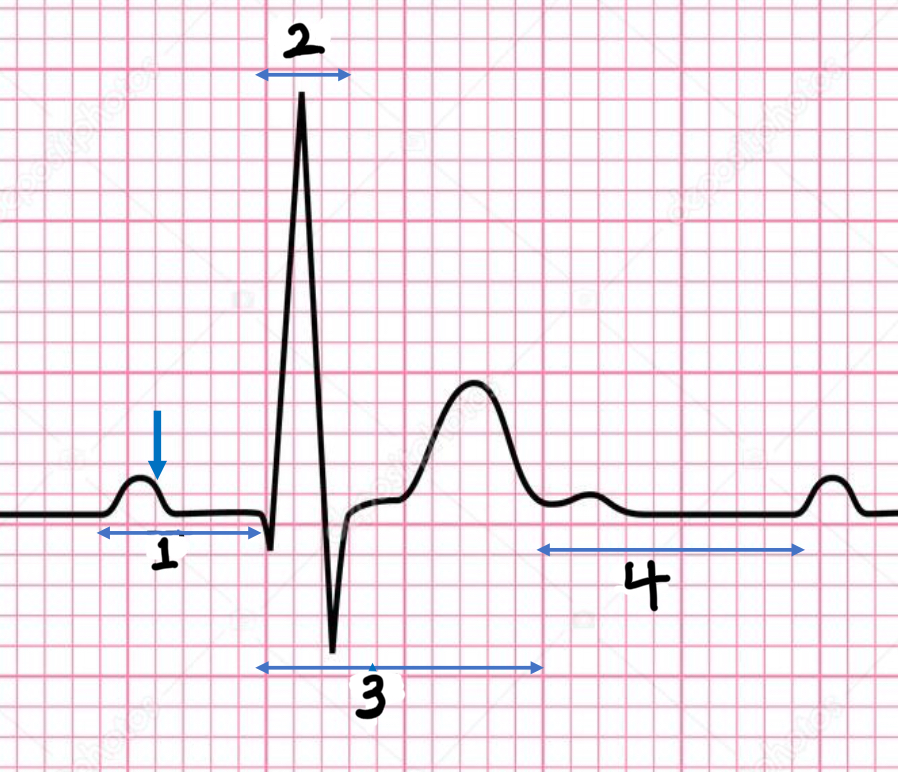

P wave

atrial depolarization

Precedes atrial contraction

QRS complex

ventricular depolarization

Precedes ventricular contraction

T wave

ventricular repolarization

PR interval

Name #1

QRS interval

Name #2

QT interval

Name #3

TP interval

Name #4

PR interval

time from beginning of the P wave to the beginning of the QRS complex

QRS interval

Time from beginning of the QRS complex to the end of the QRS complex

QT interval

Time from beginning of QRS complex to the end of the T wave

TP interval

Time from end of T wave to the beginning of P wave